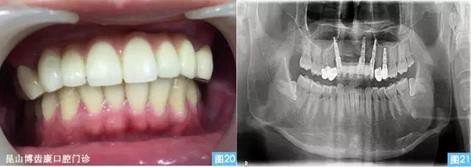

圖20圖21:(圖20左)完成最終修復(fù)后的口內(nèi)照,(圖21右)種植術(shù)后12個月曲面體層攝影。